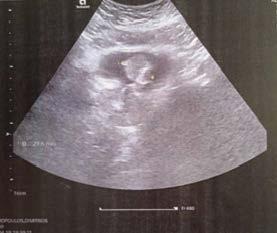

A 50-year-old patient with no prior history of hematuria was presented to the outpatient department reporting an episode of intermittent urinary mucosal secretion aggravated by the appearance of macroscopic hematuria. Abdominal ultrasound revealed a mass at the expense of the anterior wall of the bladder (Figures 1a and 1b). Computed tomography showed calcifications of the bladder dome while no lesion was noted outside of the bladder wall. The cystoscopy visualized a twin tumor arising mainly from the superior wall with unusual appearance. The left tumor was yellowish and had gross mucinous multinodular appearance while the right was whitish and had a solid configuration, partially covered by urothelium with reactive changes (Figure 2a). An extended transurethral resection of the tumor was performed (Figure 2b). The histology revealed adenocarcinoma with poorly differentiated areas showing solid rudimentary tubular architecture and areas with focal mucinous differentiation characterized by local mucus production with signet ring cells floating in mucinous lakes. Focal areas of normal urothelium and nests of Von Brunn were also present (Figure 3b). The above tumor extended invasively to parts of the muscular layer of the bladder wall. The immunostains revealed cytokeratin 20 (CK20), CK7 and CDX2 expression, CEA, EMA, P53, Ki67CD15/LeuM1 expression and absence of expression for Cata 3, CK903, chromogranin A, synaptophysin, NKX3-1, Ca125, p63, B catenin. According to the pathologist, histological study revealed a rather unusual AU. A thoracic CT scan and a virtual colonoscopy were performed showing no obvious sites of distant metastases, or primary disease of the bowel. MRI of the pelvis showed no evidence of urachal remnant. The patient asked for a